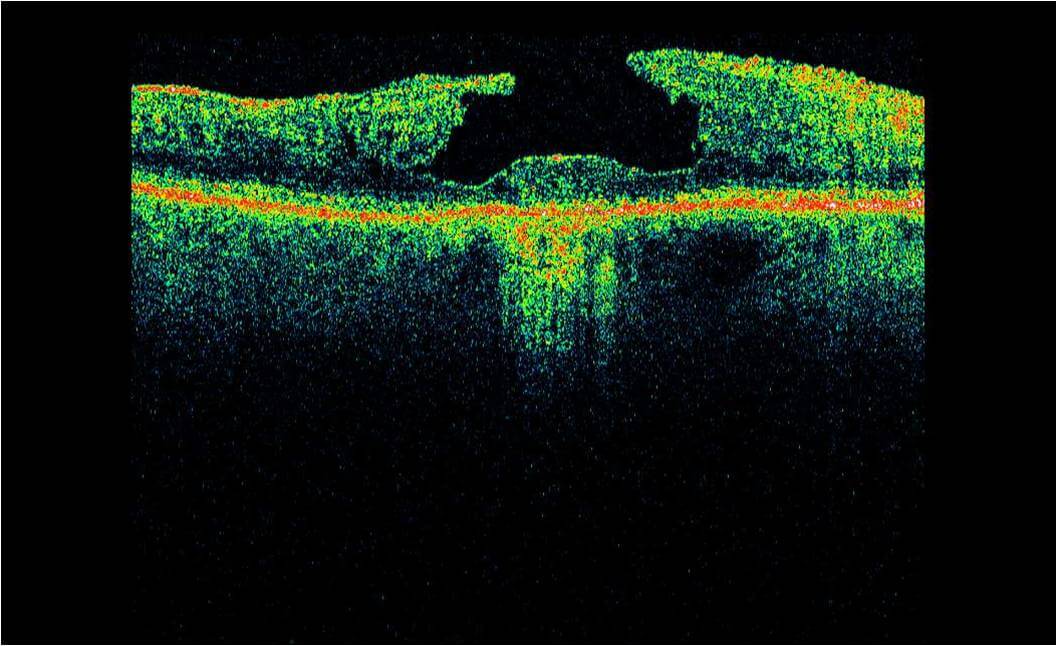

Optical Coherence Tomography (OCT) is an advanced eye scan, similar to ultrasound. The OCT uses light rather than sound waves to illustrate the different layers that make up the back of the eye. Within 2 seconds, the OCT takes over 30,000 individual scans of the back of the eye and this is used to produce a 3D image of the retina and optic nerve. The scan gives an accurate cross-sectional map through the retina and allows examination of the back of the eye in incredibly fine detail.

The OCT also captures a digital photograph of the surface of the eye at the same time, and this can then be cross-referenced with any areas of concern.

The scan shows us beneath the surface of your retina, so we can see and better understand the very fine changes which can be indications of something unhealthy or abnormal.